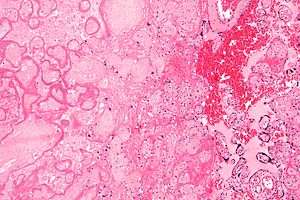

| Micrograph of a placental infarct (left of image), a cause of intrauterine hypoxia. H&E stain. | |

Intrauterine hypoxia occurs when the fetus is deprived of an adequate supply of oxygen. It may be due to a variety of reasons such as prolapse or occlusion of the umbilical cord, placental infarction and maternal smoking. Intrauterine growth restriction (IUGR) may cause or be the result of hypoxia. Intrauterine hypoxia can cause cellular damage that occurs within the central nervous system (the brain and spinal cord). This results in an increased mortality rate, including an increased risk of sudden infant death syndrome (SIDS). Oxygen deprivation in the fetus and neonate have been implicated as either a primary or as a contributing risk factor in numerous neurological and neuropsychiatric disorders such as epilepsy, ADHD, eating disorders and cerebral palsy.[1][2][3][4][5][6]